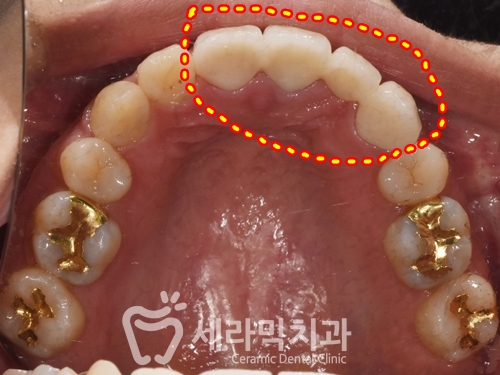

치아교정 후 앞니(#22)를 상실하고 브릿지 치료를 하신 후

시간이 지나면서 치아가 돌출되고 앞니가 벌어졌습니다.

① 앞니 돌출

② 치아 사이 벌어짐

③ 기존 보철물 노후화

치아교정 후, 앞니 가 다시 벌어지지 않도록

보철물을 새로 제작하였습니다.(4개 치아를 연결하여 보철물 제작)